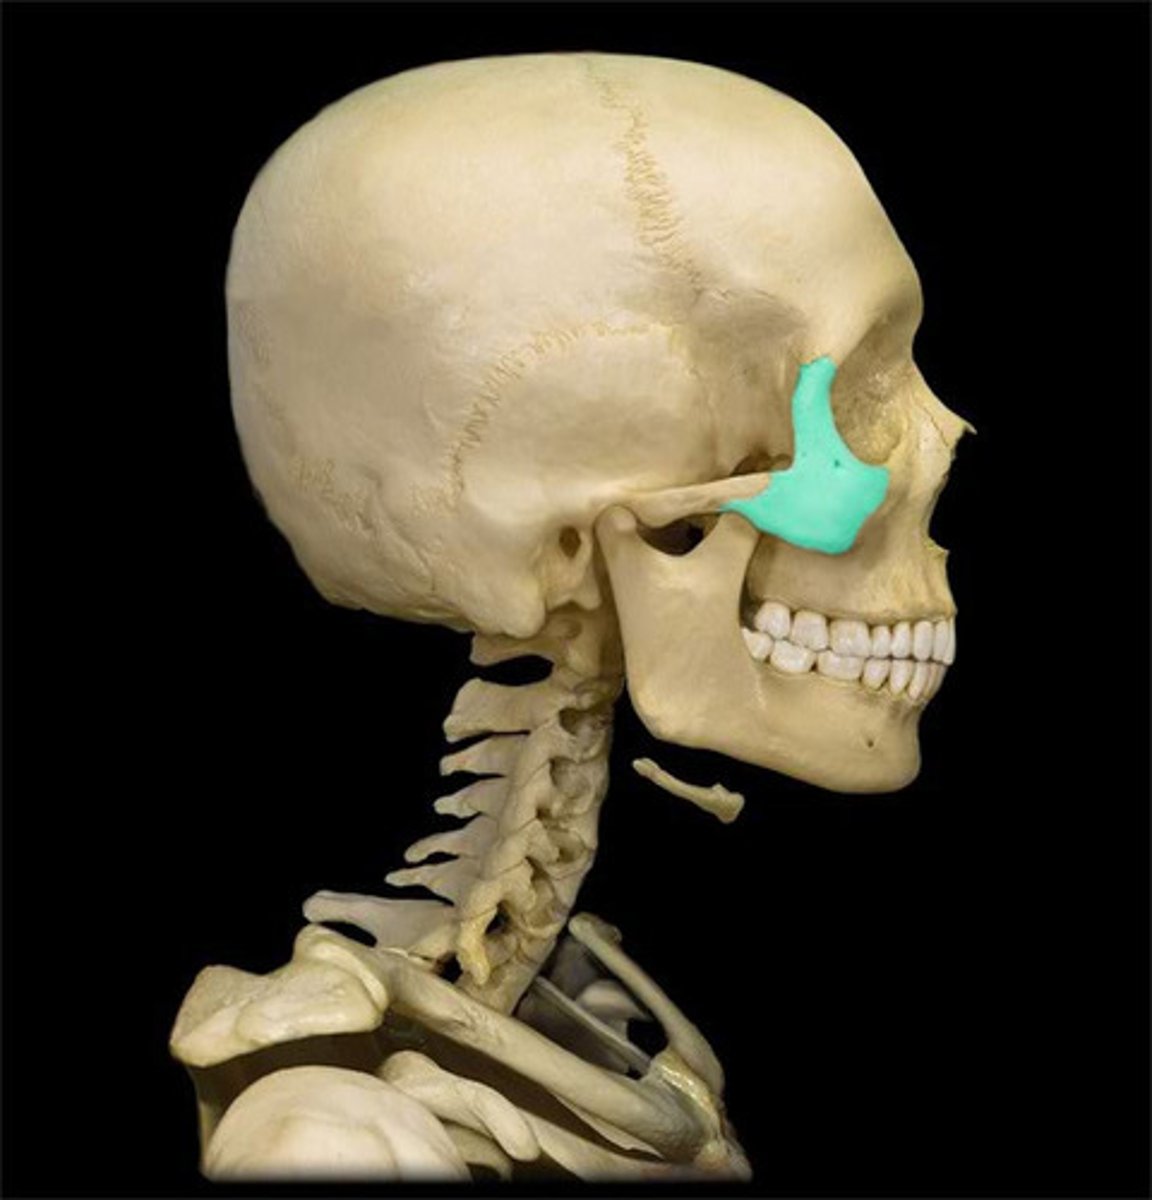

zygomatic bone

temporal process of zygomatic bone

zygomatic arch